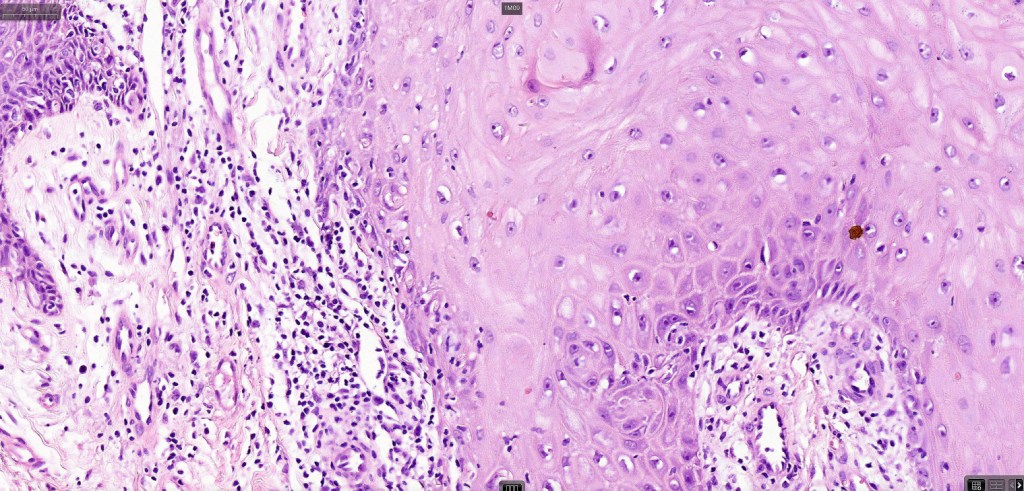

•Well differentiated squamous epithelium often with a characteristic ground-glass appearance

•Only mild pleomorphism & basally located mitoses

Below is a fascinating case shared on McKee Derm by Dr. James Simpson. There is an obvious keratoacanthoma but at the edge of the lesion there is marked atypia with nuclear enlargement and pleomorphism. This is also evident in the adjacent epidermis and in the deeper nests.